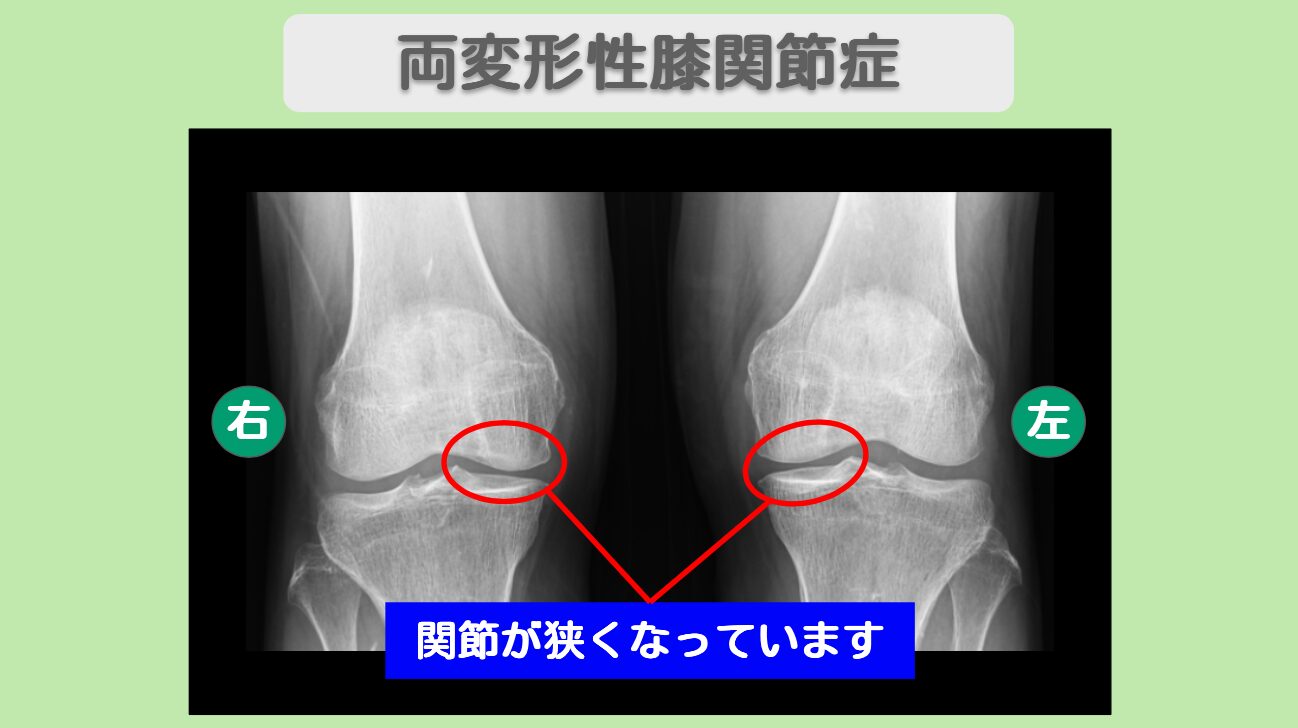

MRI・レントゲン所見

MRIにてヘルニアと狭窄を認めます。